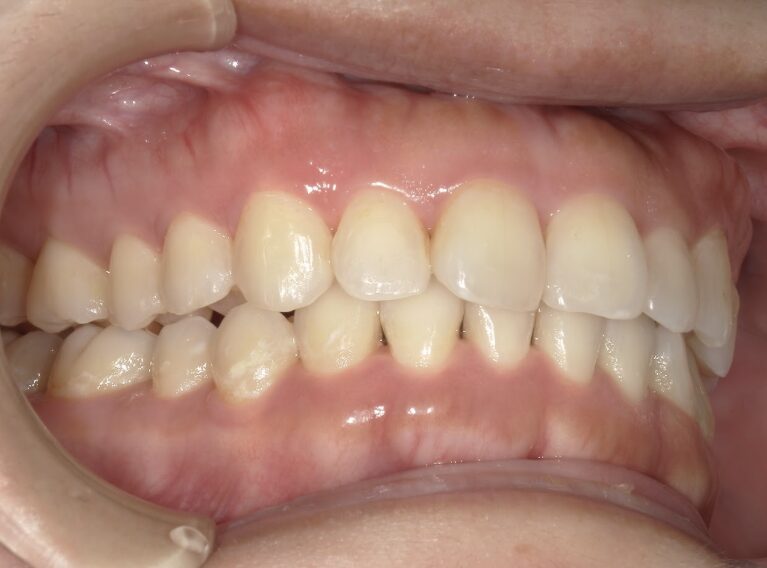

過蓋咬合

ガタガタを主訴に当院を受診され、上下前歯部に叢生(ガタガタ)と過蓋咬合(上の歯が下の歯を深く覆いかぶさっている状態)を認めました。

IPRを使用してマウスピース型矯正装置(インビザライン)を使用し過蓋咬合及び叢生の改善を行いました。

年齢/性別30代女性

抜歯部位非抜歯

治療期間1年6ヶ月